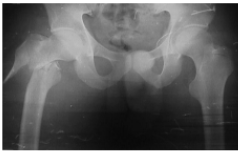

Fractura presente en esta radiografia

Intertrocanterica

Mecanismo de lesion de esta fractura

Jovenes: Alta energia

Ancianos: Caisa simple, impacto directo en trocanter mayor

De acuerdo a la clasificacion de EVANS esta fractura se considera

Inestable

Estable

Tratamiento de fractura intertrocanterica

Idealmente <48hrs post lesion

Clavo endomedular con tornillo deslizante

Tratamiento de fractura intertrocanterica en pacientes con comorbilidades graves

Protesis parcial (De Thompson)